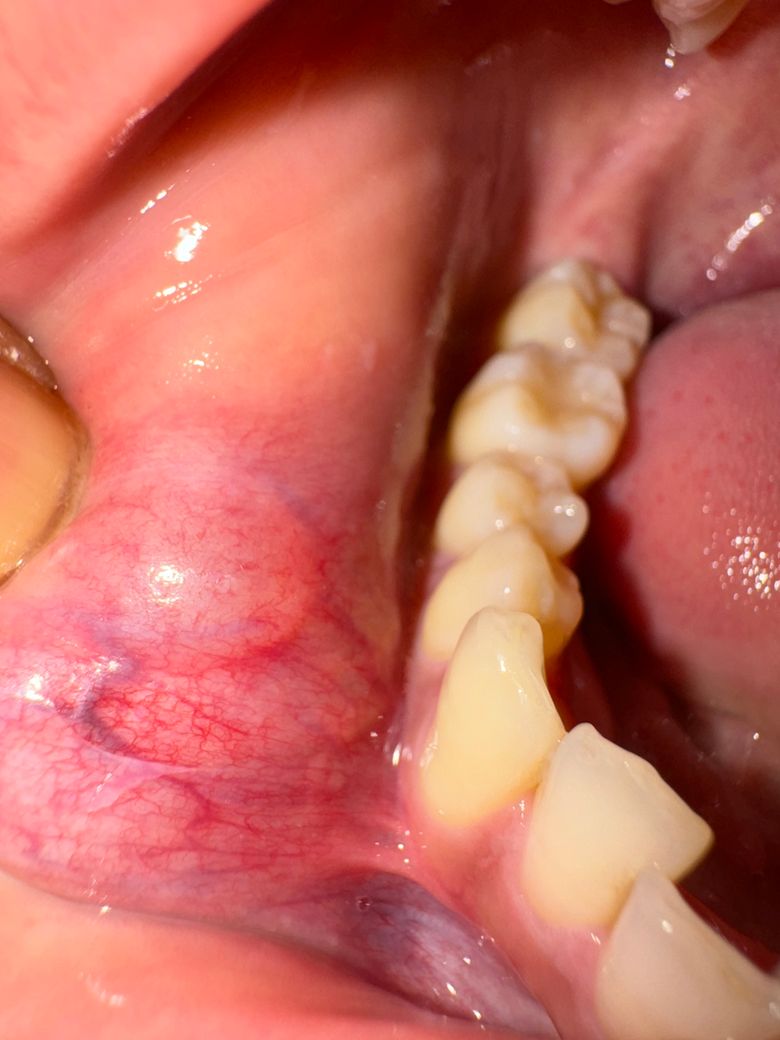

안녕하세요 몇주 전에도 글을 올렸었는데

맨처음엔 이런 상태였고 2주뒤엔

• 1번 째 사진